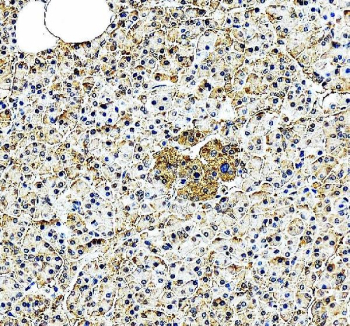

EIF2A Antibody Pancreas IHC. Immunohistochemistry analysis of FFPE human pancreas tissue stained with EIF2A antibody detecting Eukaryotic initiation factor 2A. Cytoplasmic staining is observed in pancreatic cells with moderate intensity and a granular distribution, consistent with EIF2A localization in ribosome-associated translation machinery and involvement in non-canonical protein synthesis. The staining highlights both exocrine and endocrine cellular compartments, with nuclei counterstained blue. HIER: heat-mediated antigen retrieval in pH 8 EDTA buffer.